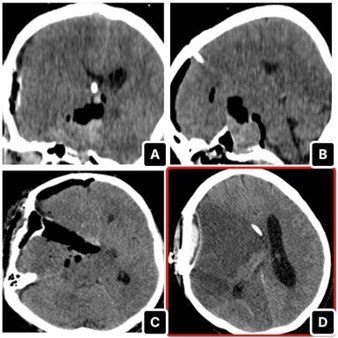

Given the lesion’s size and intraventricular extension, the patient underwent pterional craniotomy for debulking as the first step of tumor excision (Figure 2). shows the tumour debulking and the identification of the right Middle Cerebral Artery (MCA). As the MCA was promptly identified during the operation, local irrigation with papaverine solutions was applied. Postoperatively, the patient was transferred again to the ICU, and CT head showed the extent of debulking (Figure 3). Two days post-op, the patient developed anisocoria, and the repeated CT scan showed a right-sided MCA infarct with extensive midline shift (Figure 3). No matter the intra-operative papaverine irrigation, MCA vasospasm was quite evident. Therefore, we did not continue with further endoscopic transsphenoidal resection. The patient subsequently succumbed to complications.